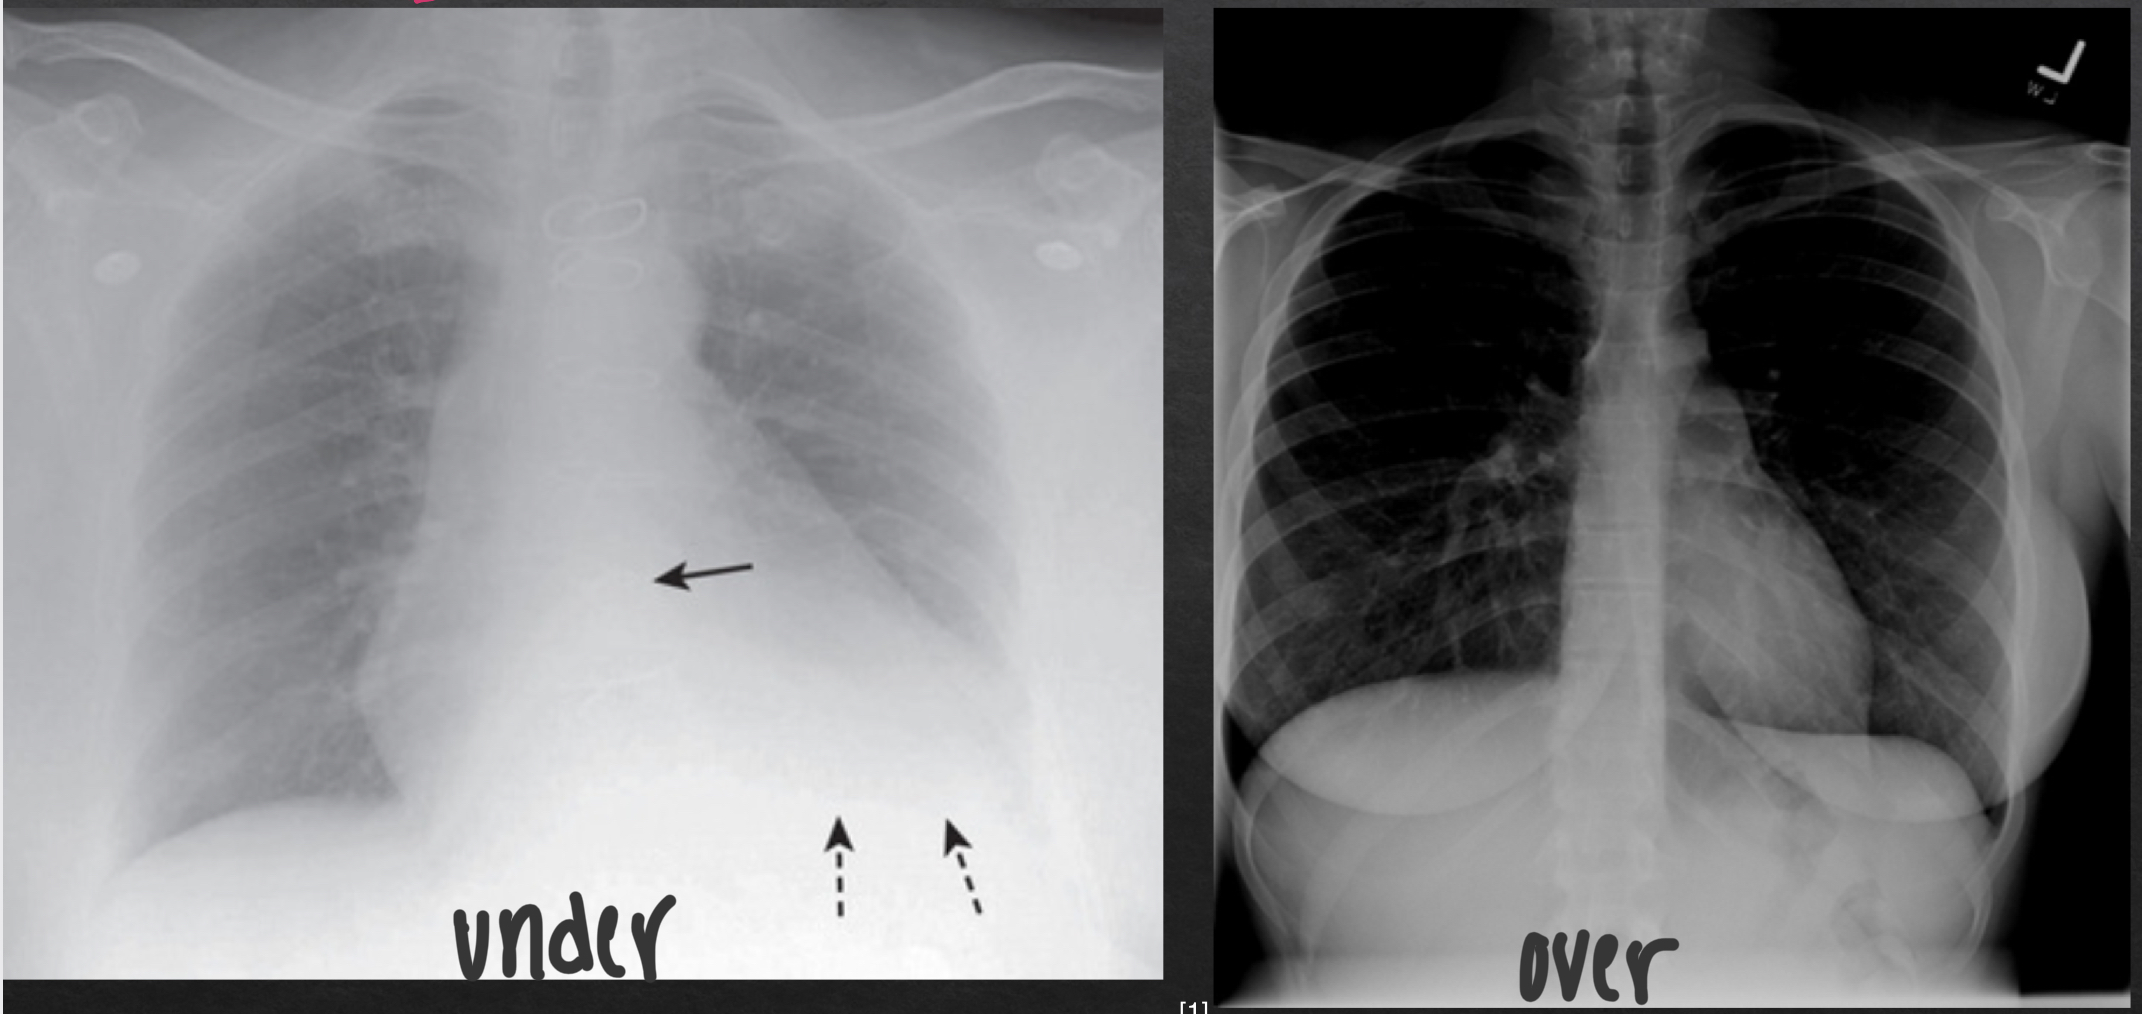

underpenetrated vs overpenetrated CXR

penetration of chest xray

degree to which xrays have passed through the body

adequate penetration:

outline of the thoracic spine visible through heart

inadequate penetration

can mimic or hide disease